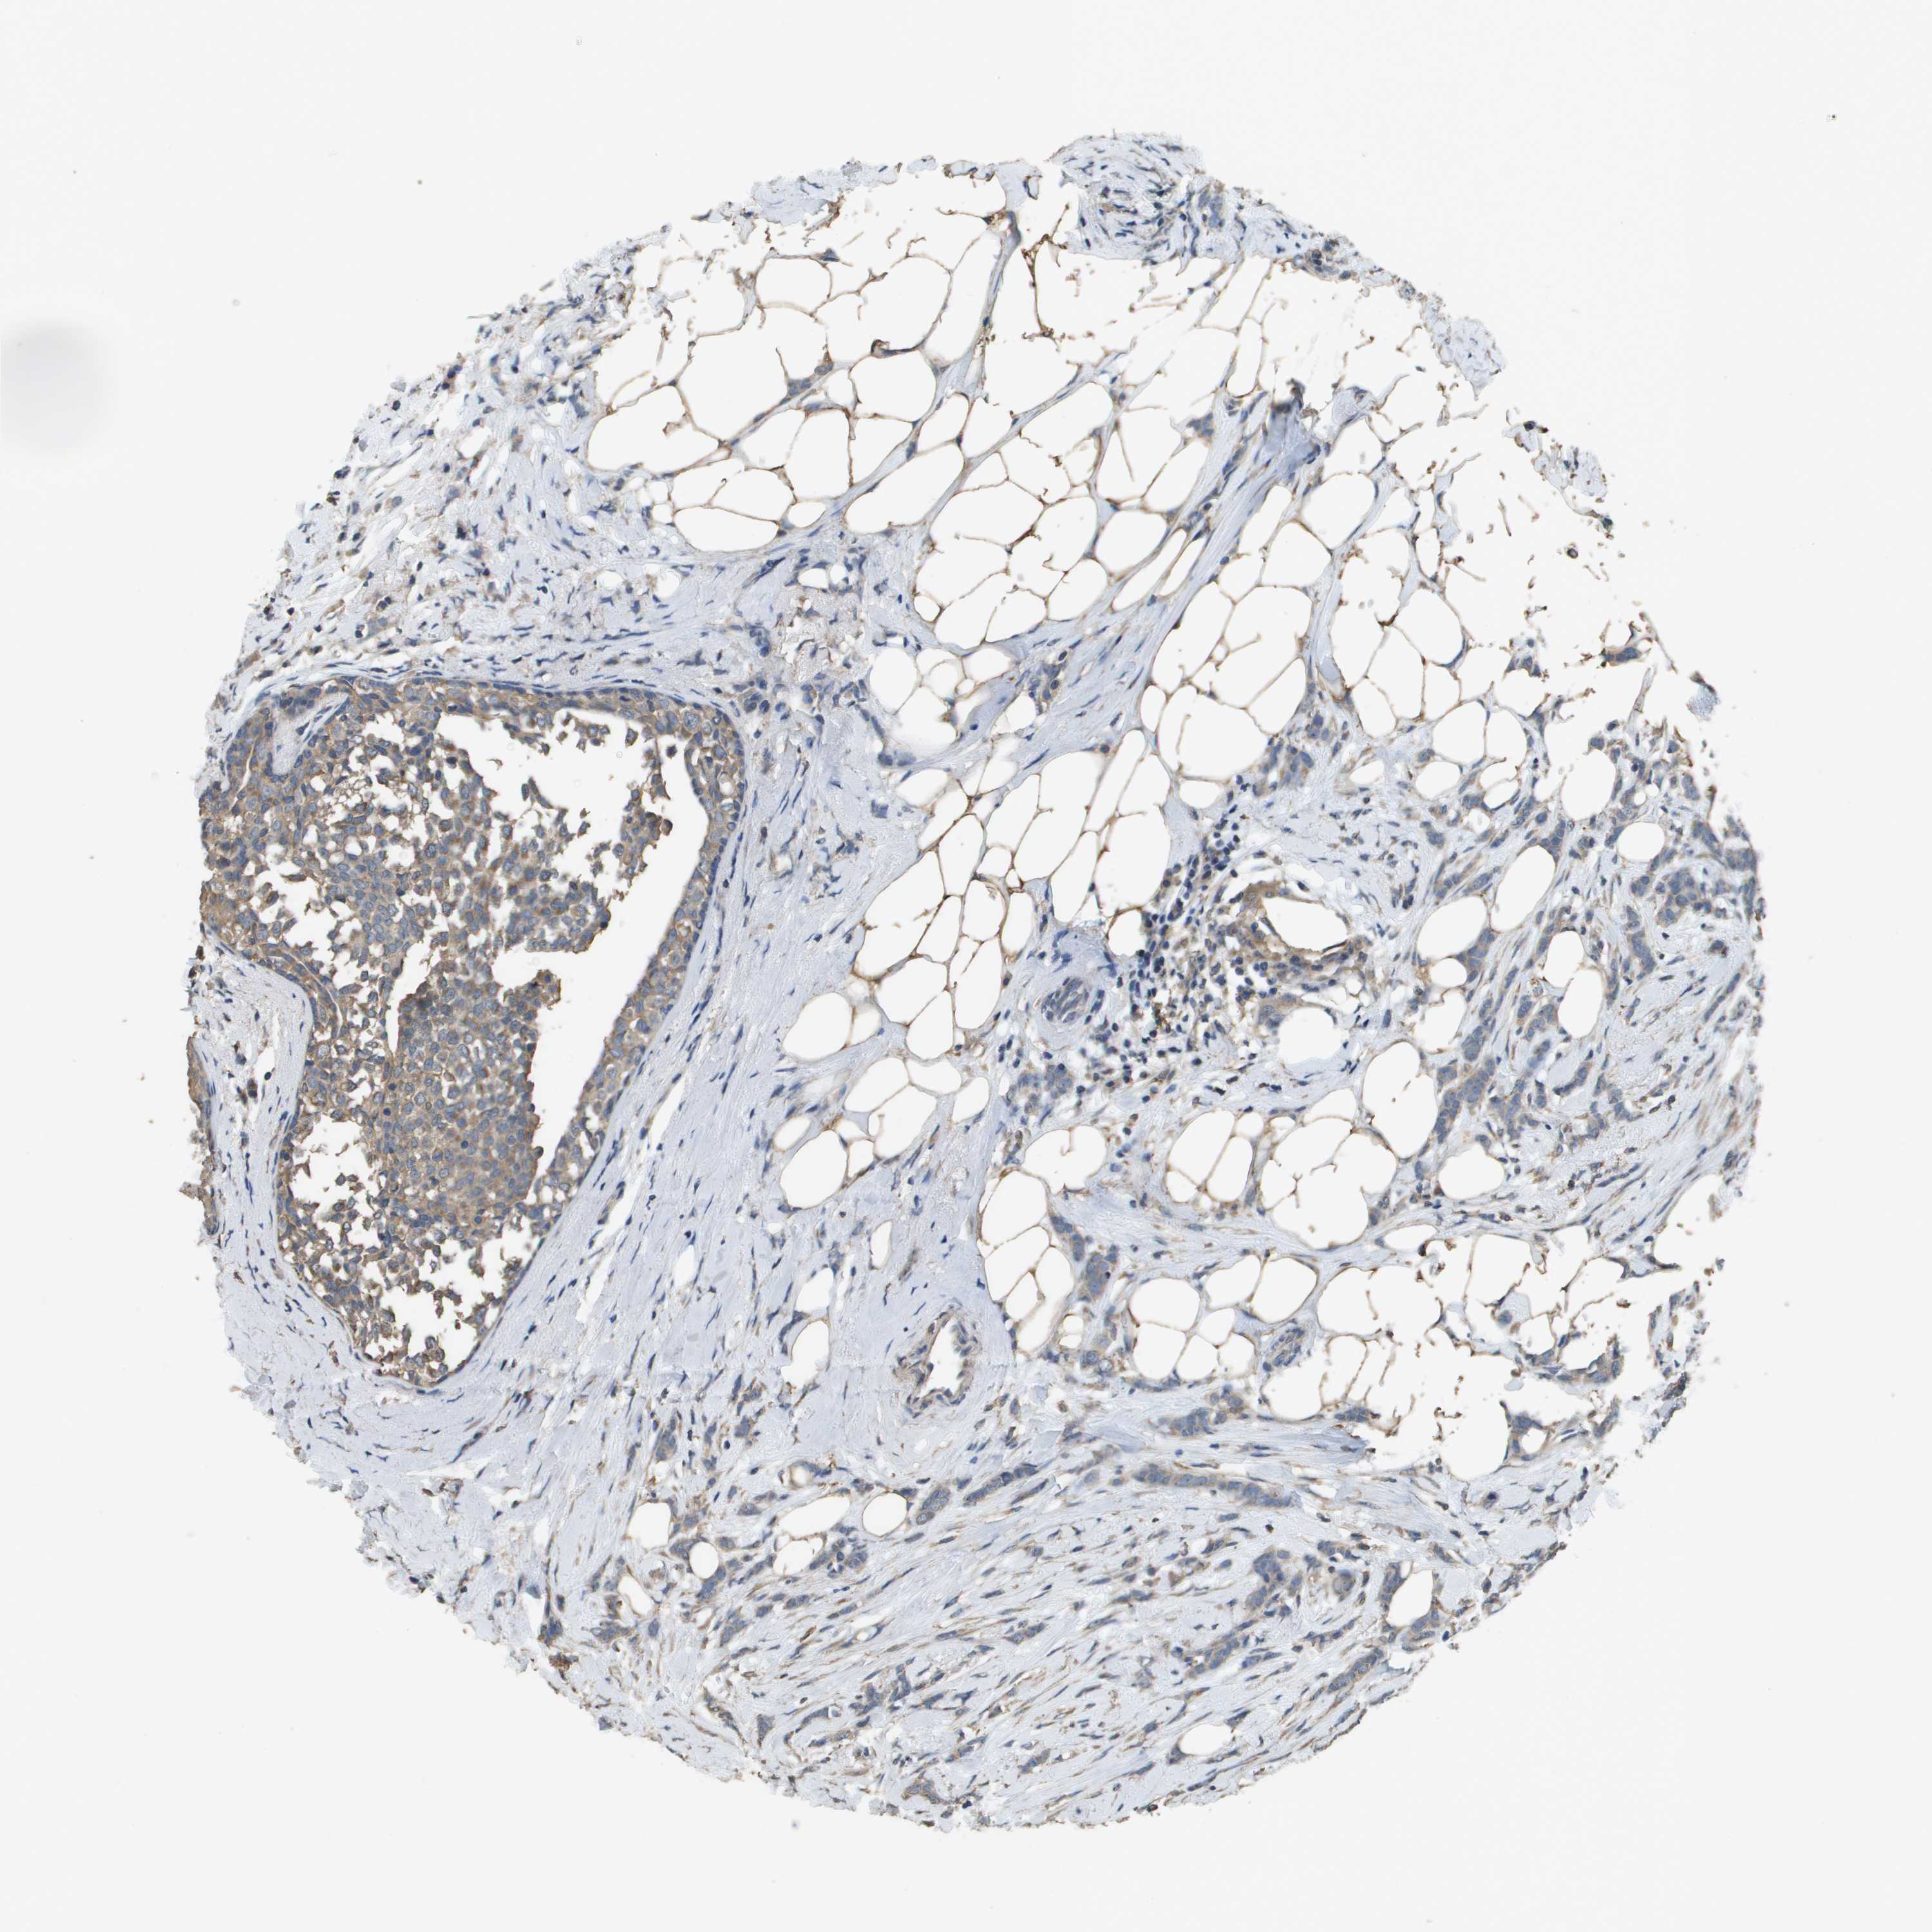

CANCER BREAST CANCER Show tissue menu

BRCA TCGA BRCA VALIDATION PROTEIN EXPRESSION